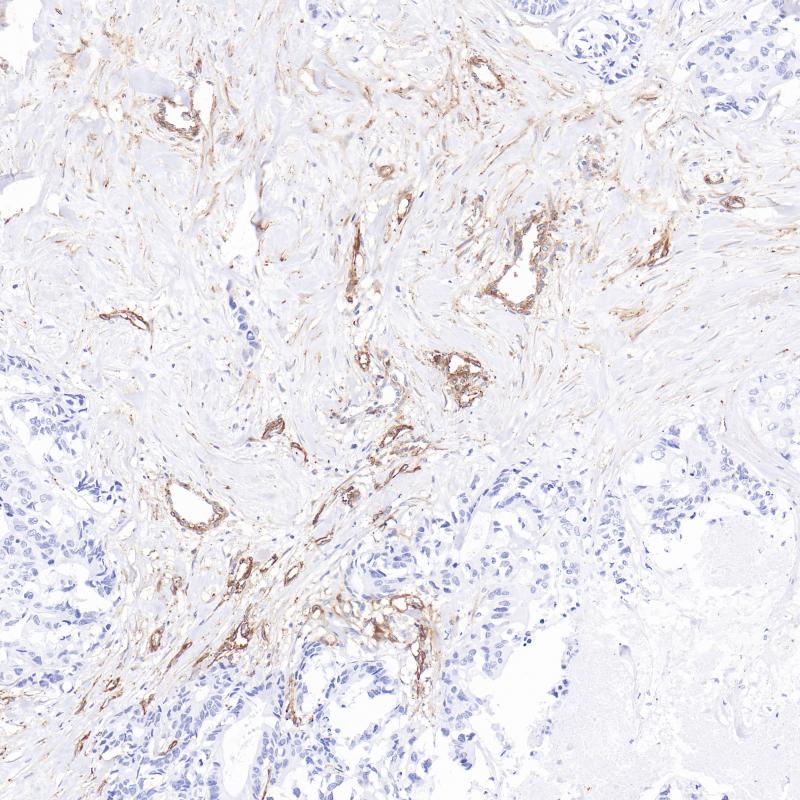

肝细胞肝癌AFP(BP6244)染色

甲胎蛋白(AFP)是一种存在于哺乳动物胎儿肝脏、卵黄囊和胃肠道的糖蛋白。AFP在成人正常细胞中表达较低,但在成人肝癌细胞中异常表达。肿瘤抑制基因p53和β-catenin都参与了AFP表达的调控。在正常的成年细胞中,p53结合到AFP基因的抑制区,从而阻断转录。p53和β-catenin的突变均与AFP的异常表达有关。研究表明,血清AFP水平升高是肝细胞癌的预测指标。AFP在成人肝组织中不表达,但在成人肝癌细胞中异常表达。AFP主要用于肝细胞癌的临床诊断。

阳性对照

肝细胞肝癌

亚细胞定位

细胞质